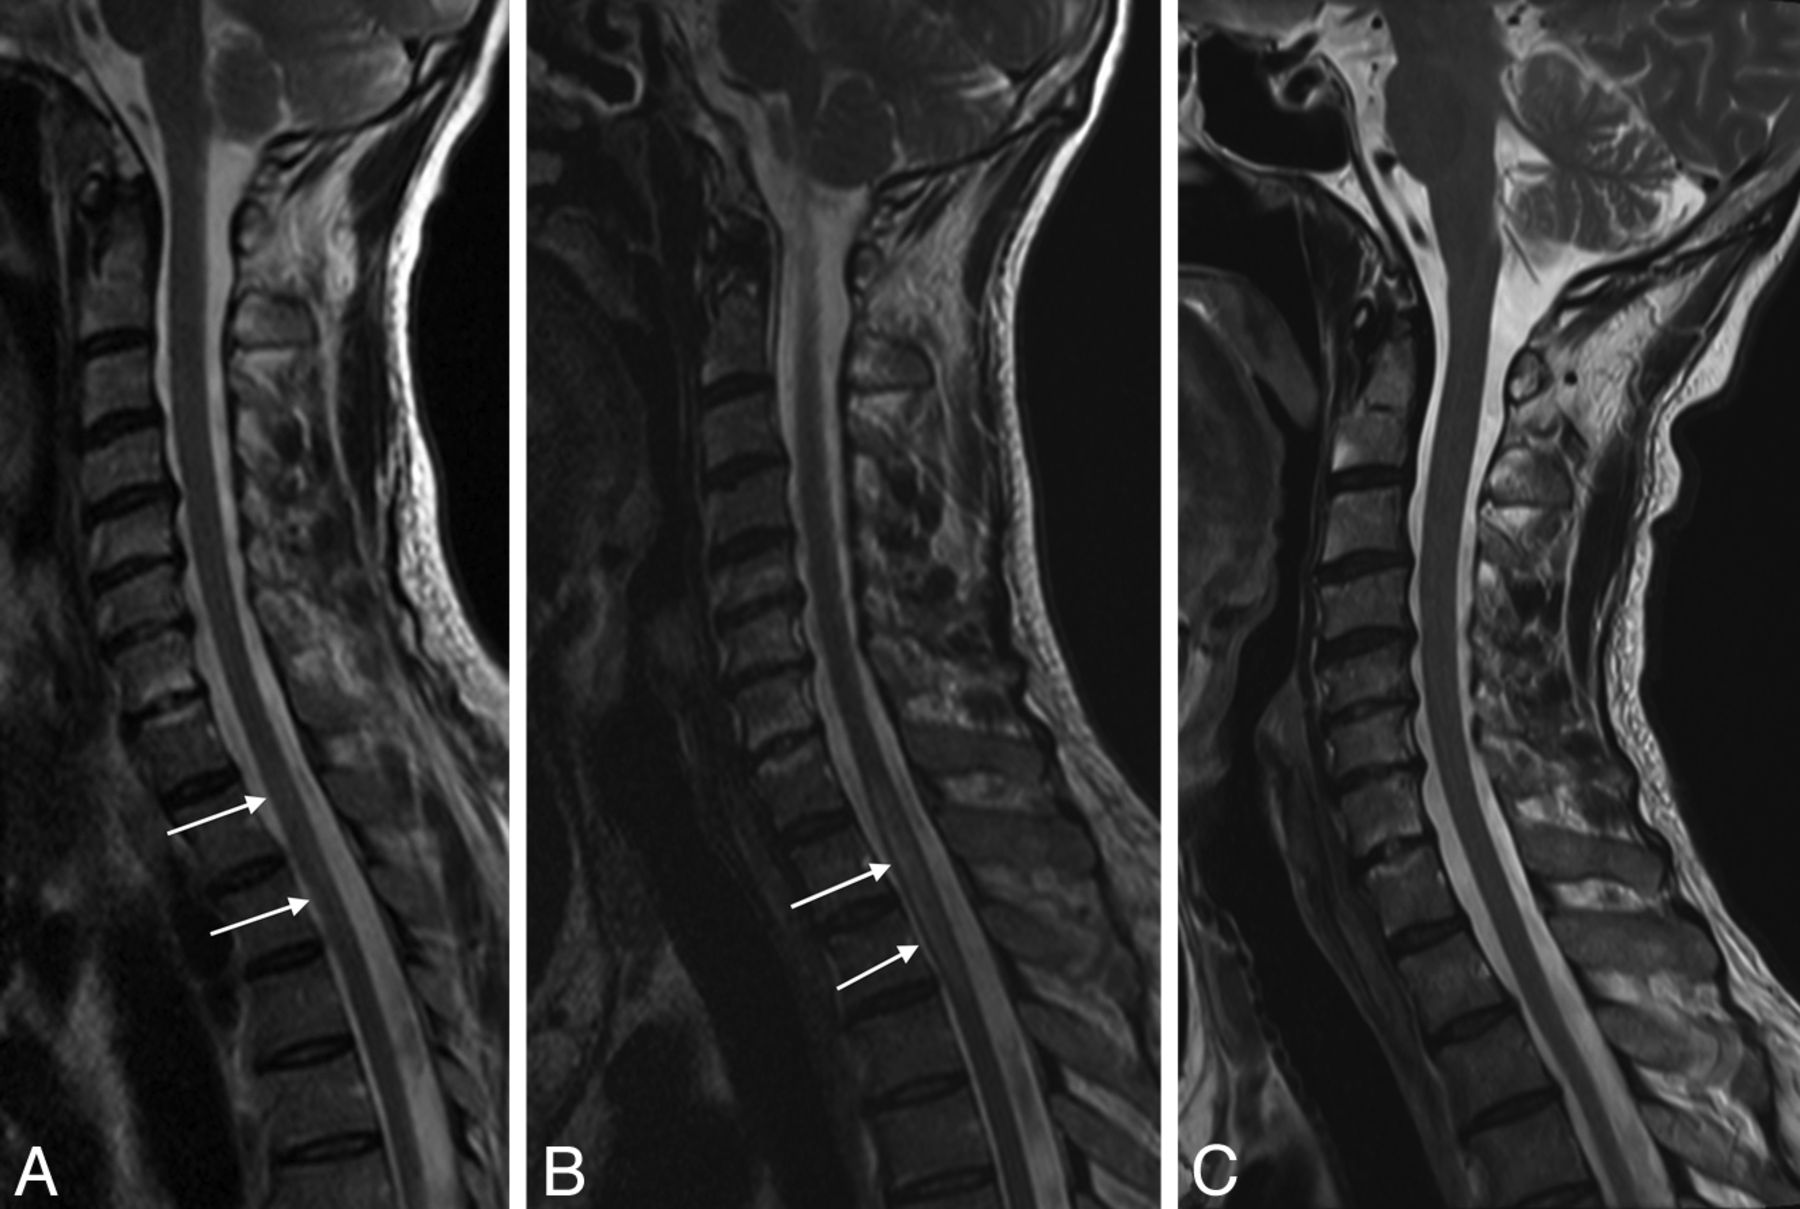

Reversible cervical spinal cord lesion due to decompression sickness. MR imaging shows an extensive lesion causing enlargement of the cervical spinal cord. The lesion appears as a high signal on sagittal (A) and axial T2WI (D and E) and on DWI (B) without concomitant signal decrease on the ADC map (C). All these characteristics, with complete healing without a scar as shown on sagittal T2WI (F) obtained 2 weeks later, are consistent with vasogenic edema (referred to as an “ischemic-like” lesion in the On-line Table).

Reversible thoracic spinal cord lesion due to decompression sickness. MR imaging performed 24 hours after the diving accident shows a thoracic lesion appearing as a high signal on sagittal T2WI (A, white arrows). The lesion increases in size on the following day (B, white arrows) and subsequently disappears on day 13 (C). This evolution may also be consistent with edema.

On the other hand, various radiologic and histopathologic findings have been published to support the venous infarction theory. First, the more frequent occurrence of lateral and posterior column white matter lesions compared with gray matter lesions in spinal cord decompression sickness is more likely a consequence of an obstruction of the slow-flowing epidural venous bed by nitrogen bubbles, which leads to vasogenic edema (Figs 1 and 2).5,8 In some cases, there may be additional venous infarction (Fig 3B, -C). Similar lesions have been provoked experimentally in dogs.9 Second, several histopathologic studies have demonstrated venous obstruction and white matter congestion.45,46 Third, vasogenic edema, appearing as high signal on both DWI and ADC maps, was observed by Vollmann et al in 201147 in a case of spinal cord decompression sickness, also suggesting a venous rather than arterial pathologic process.